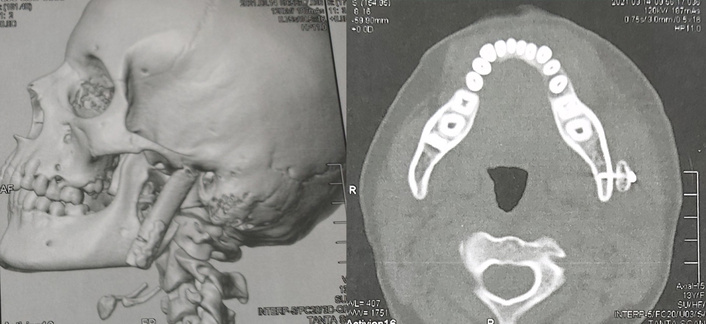

All patients’ mandibular condyle reconstructions using the costochondral graft were effective, according to postoperative CT scans, and every rib suited the lateral surface of the ramus perfectly. The titanium plate and screws were precisely secured, and the postoperative position of the bone grafts was comparable to the normal position of the mandible in relation to the glenoid fossa (Figure 4).

Postoperative 3D and axial computed tomography show costochondral graft with accurate position in relation to the lateral surface of ramus. Source from case No.3.